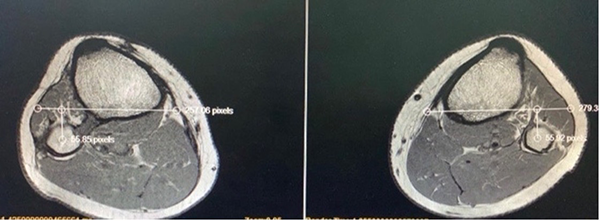

En la actualidad, con tres años de seguimiento, el paciente no presenta dolor, no refiere inestabilidad y tiene un rango de movimiento completo en su rodilla. Las maniobras de traslación anteroposteriores de peroné son negativas y no volvió a notar resaltos óseos durante la práctica deportiva. Se realizaron radiografías en estrés que no muestran diferencia con la rodilla contralateral y se le realizó una RM de control que evidencia una correcta reducción de la articulación TPR y un injerto completamente incorporado (fig. 5). Actualmente realiza deportes de alta competencia sin limitaciones.

Figura 5: Resonancia magnética de control. Corte axial. Se observa igual distancia tibioperonea en ambas rodillas.